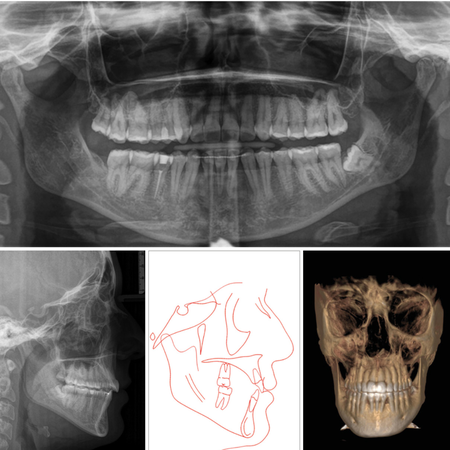

Extreme dentoalveolar compensation of a severe skeletal anterior open bite with Invisalign®

INTRODUCTION: Anterior open bite is a challenging malocclusion, often associated with skeletal and vertical discrepancies. With the evolution of clear aligner technology, Invisalign® has become a viable option for treating complex cases...

invisalign Clear aligners Anterior open bite

Compensación dentoesquelética extrema para mordida abierta anterior esquelética severa tratada con Invisalign

INTRODUCCIÓN: : La mordida abierta anterior es una maloclusión compleja, a menudo asociada con discrepancias esqueléticas y verticales. Con la evolución de la tecnología de alineadores transparentes, (los alineadores) Invisalign® s...

invisalign® Alineadores transparentes Mordida abierta anterior